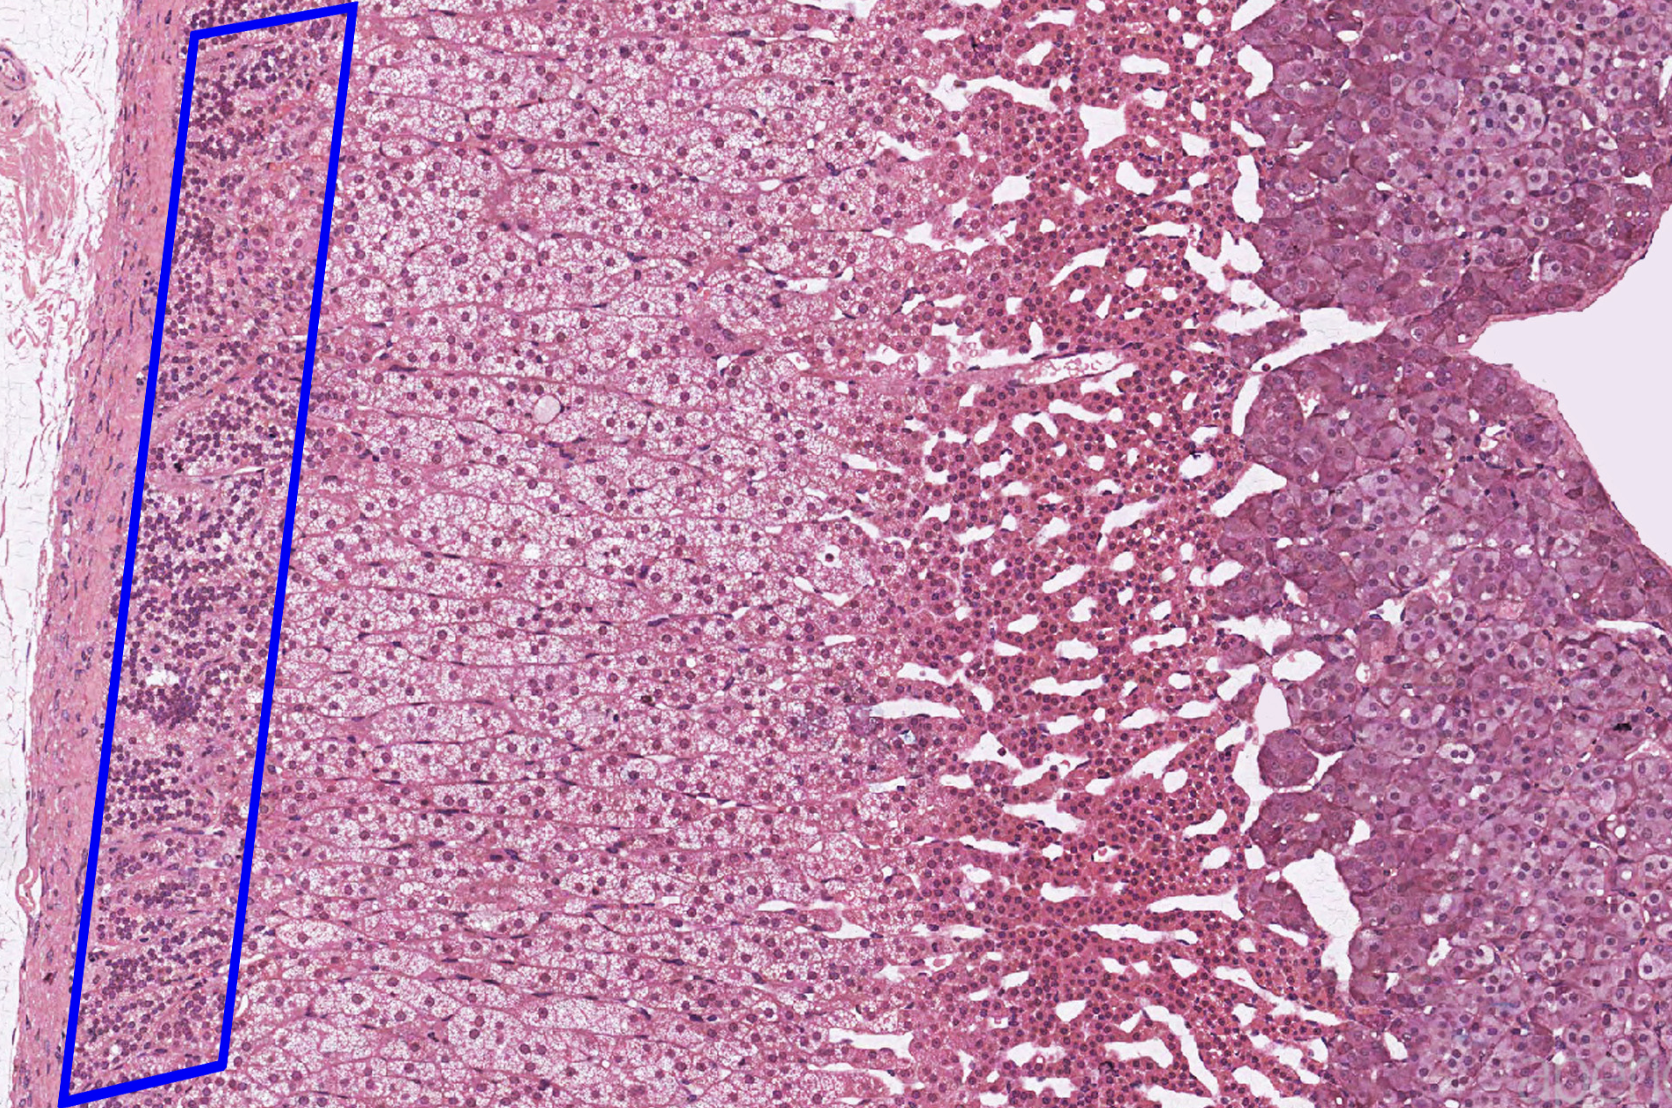

adrenal cortex

zona glomerulosa

zona fasciculata

zona reticularis

adrenal medulla